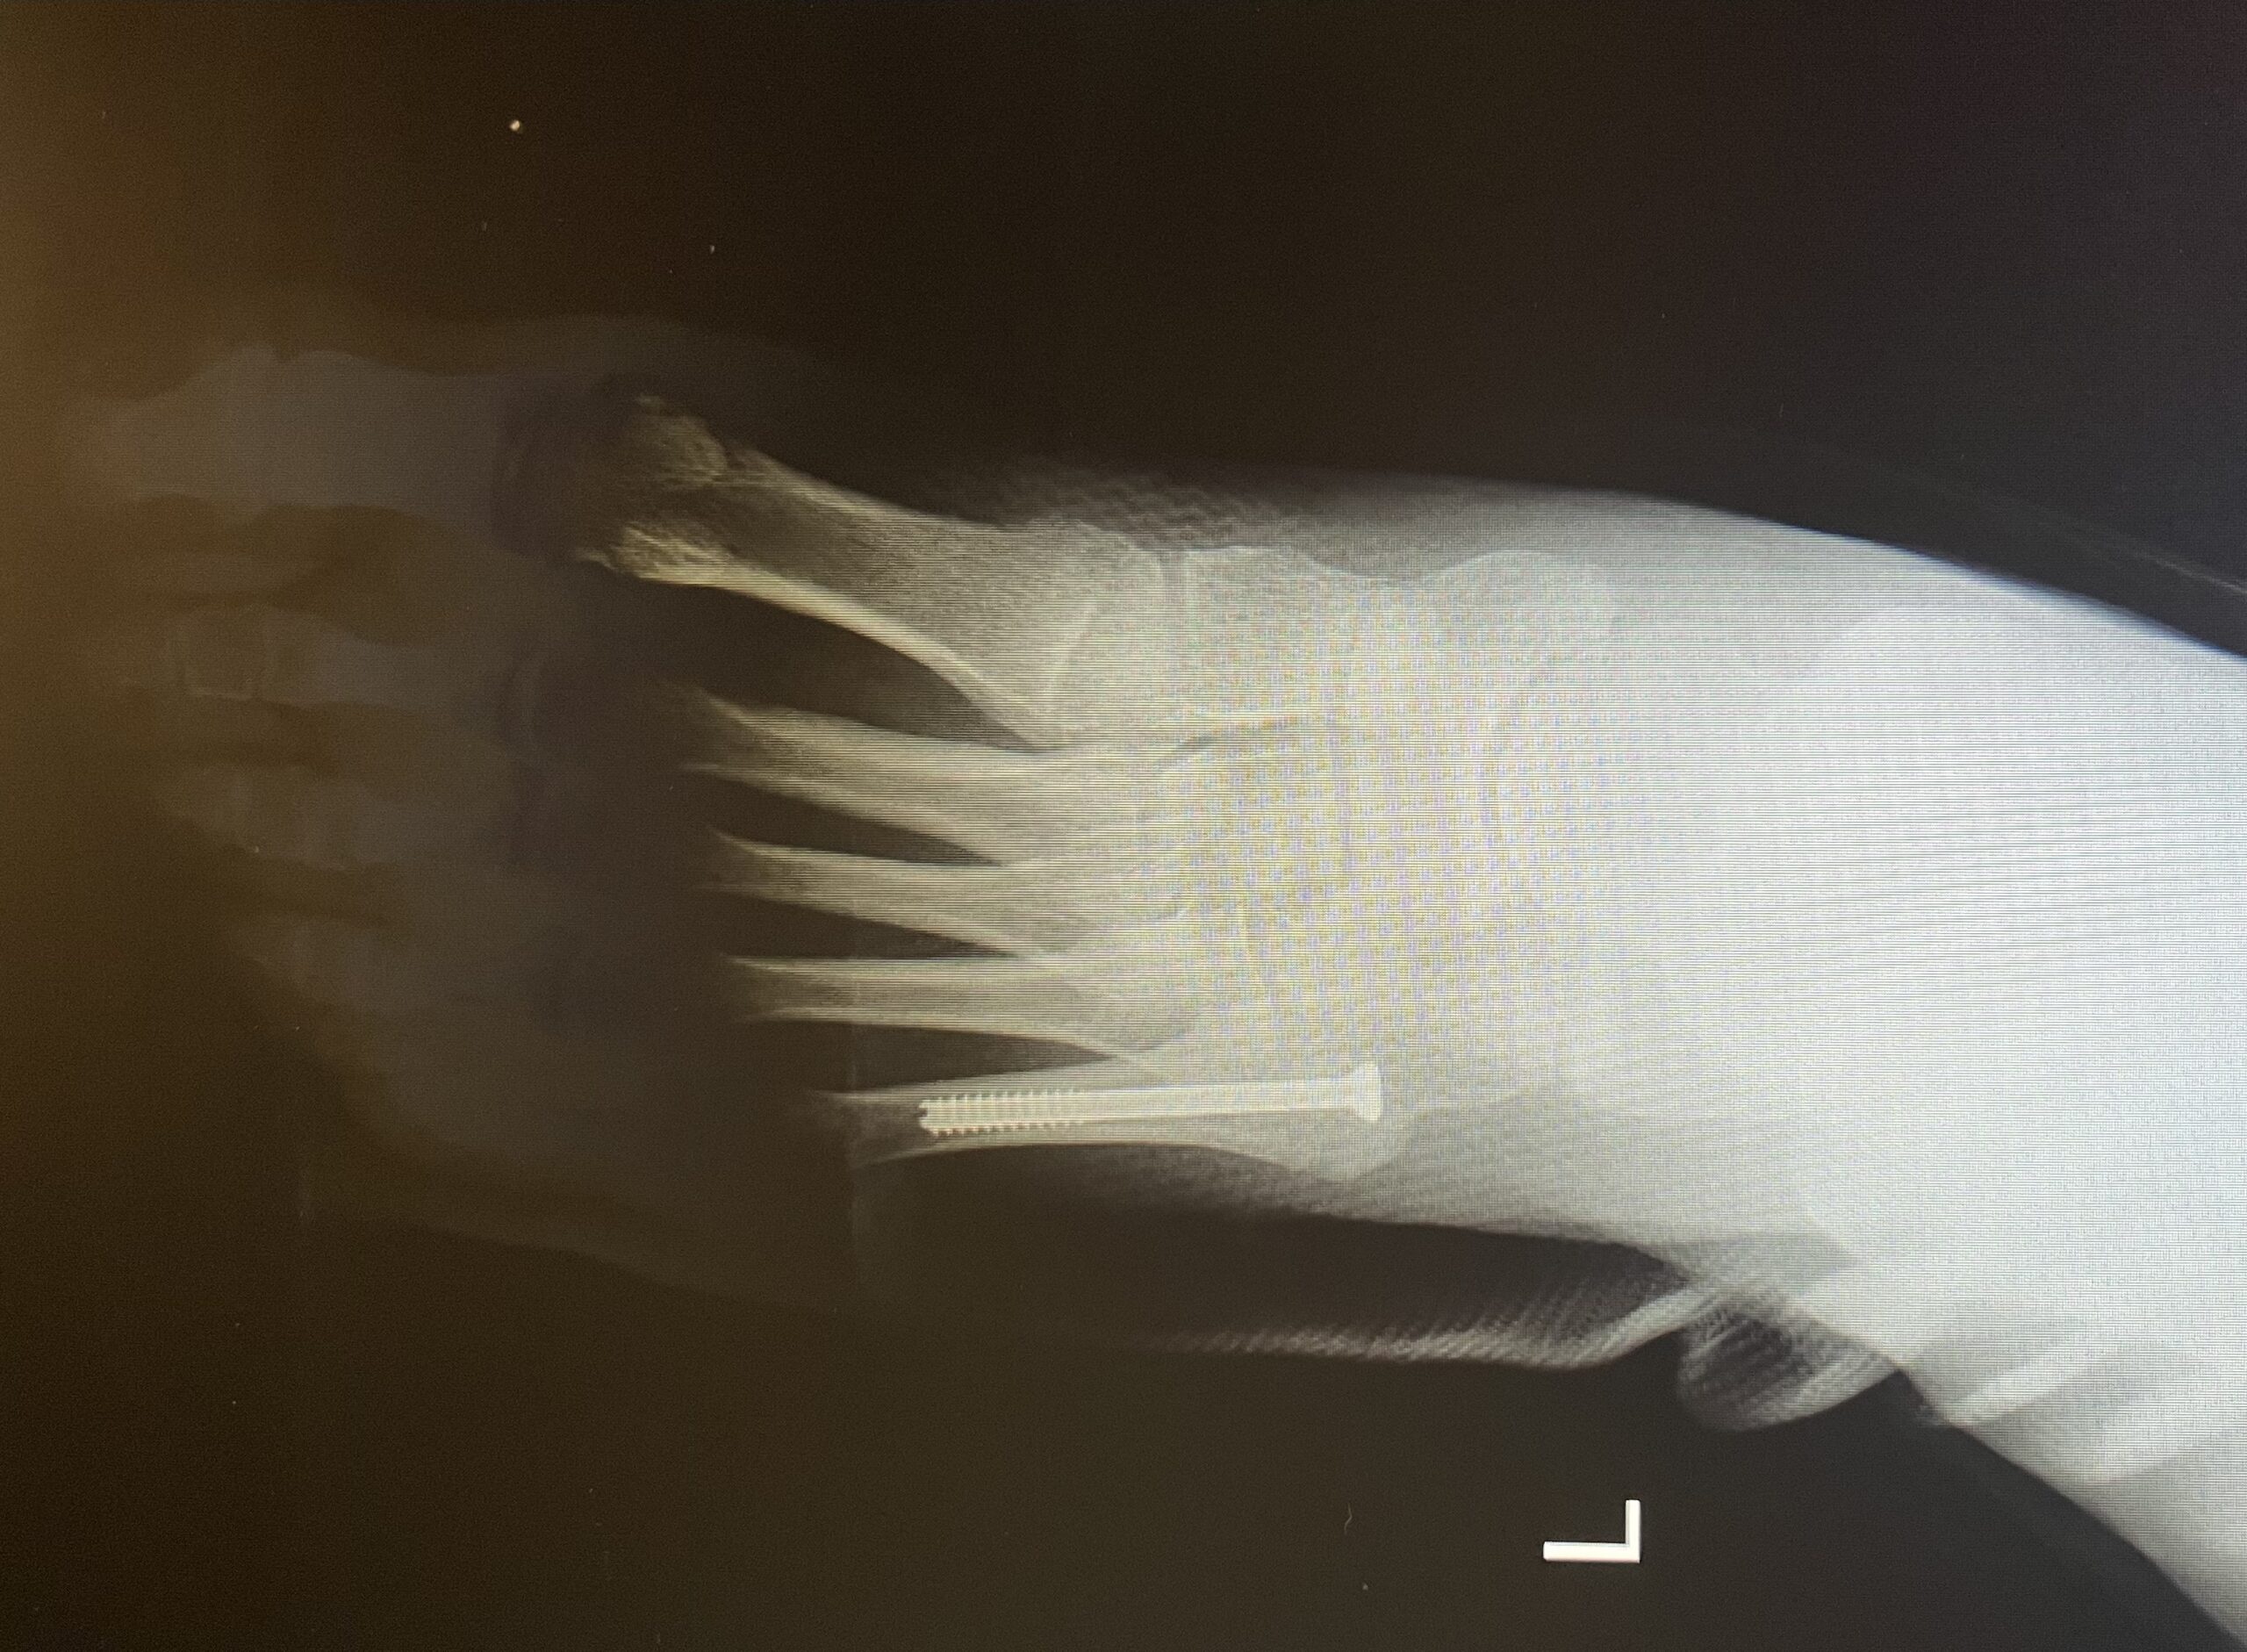

Η μέθοδος οστεοσύνθεσης ενός κατάγματος Jones συνίσταται στην τοποθέτηση ενός ενδομυελικού κοχλία, διαδερμικά. Η επάνοδος του ασθενούς στις καθημερινές και στις αθλητικές του δραστηριότητες επιτυγχάνεται στο μικρότερο χρονικό διάστημα.